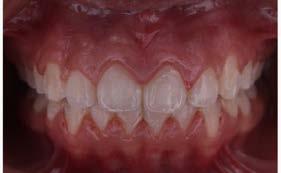

Introducción: Los principales objetivos del tratamiento ortodóncico son corregir las maloclusiones y mejorar la estética dental; sin embargo, el mismo tratamiento puede asociarse a reacciones negativas al requerir aparatología visible que altera aspectos funcionales, estéticos y de higiene oral del paciente. Estos factores podrían influir en la motivación del paciente y determinar una baja adherencia al tratamiento ortodóncico, lo que podría generar retrasos y complicaciones en la estabilización de la oclusión. Objetivo: Evaluar el nivel de satisfacción del paciente con brackets en relación con la higiene oral, el confort y la autopercepción estética. Metodología: Se trata de un estudio transversal con muestreo por conveniencia. Se evaluó el nivel de satisfacción relacionado con la higiene oral, la autopercepción estética y el confort de pacientes tratados en el Instituto mediante un cuestionario validado de autorreporte. Se realizó un análisis descriptivo de la muestra y el cálculo del puntaje del cuestionario; posteriormente, se efectuó un análisis bivariado entre las variables edad, sexo, tratamiento previo y tiempo bajo tratamiento

Higiene oral, autopercepción estética y confort en pacientes con ortodoncia

ortodóncico. Resultados: Participaron 74 pacientes con una edad promedio de 27.1 ± 8.2 años. El 55.4% (n = 41) fueron mujeres. Los hombres presentaron un menor nivel de satisfacción ( = 33.2 ± 6.4) que las mujeres ( = 35.2 ± 8.2). Aquellos pacientes que recibían tratamiento de ortodoncia por primera vez obtuvieron un menor puntaje —y, por tanto, un menor nivel de satisfacción— ( = 33.4 ± 7.6) que quienes ya habían estado sometidos a este tratamiento ( = 35.2 ± 4.6). Los pacientes con hasta 1 año de tratamiento mostraron un menor nivel de satisfacción ( = 33.2 ± 4.6) que aquellos con aparatología por más de 1 año ( = 35.1 ± 3.1). Conclusión: Es importante evaluar, en cada paciente, los factores que puedan influir de forma negativa en su calidad de vida a lo largo del tratamiento, con la finalidad de plantear intervenciones efectivas enfocadas en crear conciencia sobre las expectativas y los posibles inconvenientes derivados del mismo.

Resultados

Descripción de la muestra

En el estudio participaron 74 pacientes con una edad promedio de 27.1 ± 8.2 años. El 55.4 % (n = 41) de la muestra fueron mujeres. Según las veces que habían estado sometidos al tratamiento, el 62.1 % (n = 46) cursaban por primera vez bajo tratamiento ortodóncico, mientras que el 37.9 % (n = 28) ya habían recibido tratamientos ortodóncicos previos.

Respecto al tiempo bajo tratamiento, el 63.5 % (n = 47) llevaba hasta 1 año bajo tratamiento, y el 36.5 % (n = 27) tenía más de 1 año con aparatología ortodóncica.

Nivel de satisfacción de acuerdo con las variables estudiadas

Sexo

Los hombres tuvieron un menor nivel de satisfacción respecto a la higiene, confort y autopercepción estética que las mujeres (Tabla 4).

Número de veces bajo tratamiento

Aquellos pacientes que por primera vez recibían tratamiento de ortodoncia tuvieron un menor puntaje, es decir, un menor nivel de satisfacción que aquellos que ya habían estado sometidos a este tratamiento (Tabla 5).

Tiempo bajo tratamiento

Aquellos pacientes que tenían hasta un año con el tratamiento tuvieron un menor nivel de satisfacción que aquellos con el uso de aparatología mayor a un año (Tabla 6).